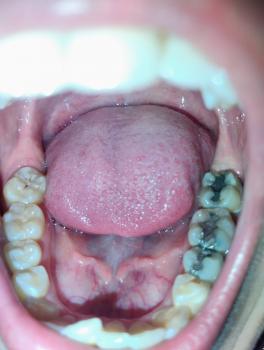

The image shows a posterior molar tooth with an old metallic (amalgam) filling. The restoration appears damaged with visible breakdown at the margins. There are signs suggesting possible secondary decay beneath or around the filling.

-

Large amalgam (silver) filling on molar

Marginal gap between filling and natural tooth

Dark discoloration around restoration edges

Possible enamel fracture near filling

Plaque retention around restoration

Surrounding gum tissue appears mildly irritated

Adjacent teeth appear intact